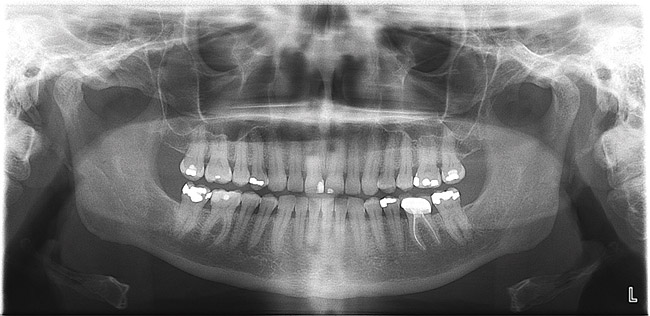

Фотографии и схемы для ОПТГ и мезиального прикуса